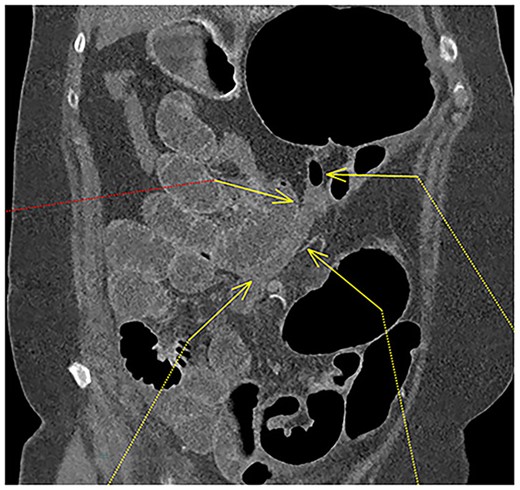

A 61-year-old female with known Marfan Syndrome was admitted to the emergency department with 3-day history of abdominal pain, nausea, vomiting and bowels not opening. Past medical history included three previous episodes of Type A aortic dissection, recent aortic root and ascending aorta replacement alongside bioprosthetic aortic valve replacement. She was an ex-smoker and usually independent at home. On presentation, the patient was haemodynamically stable and apyrexial. Biochemical results were unremarkable except for a Lactate dehydrogenase (LDH) of 309 and a C-reactive protein (CRP) of 101. On examination, she had a diffusely tender and distended abdomen, without signs of peritonism. An erect chest X-ray shows left pleural effusion with a dilated aortic root (Fig. 1). A computed tomography (CT) of thorax, abdomen and pelvis was requested, which demonstrated a caecal volvulus with a dilated cecum of 8.8 cm and upstream small bowel dilatation with air fluid levels, and a chronic aortic dissection extending from the ascending thoracic aorta to the common iliac (Figs 2–4). Following consultation between radiologists, cardiothoracic surgeons and general surgeons, she underwent an emergency laparotomy and right hemicolectomy with side-to-side ileocolic anastomosis. Intraoperatively, the caecal volvulus, comprising a dilated ascending colon measuring up to 10 cm, was delivered and resected along with its mesentery. The patient was admitted to the intensive care unit post-operatively for close blood pressure monitoring and control and stepped down to level 3 wards on day-2 post-operation. Her operation was complicated by a small infected wound haematoma thatwas managed with a 5-day course of ciprofloxacin. A CT of the abdomen and pelvis to investigate a rising CRP on day-9 revealed a subcapsular liver haematoma thath was managed conservatively. The patient was discharged 12-days post-operatively. Histology from the resected colon showed evidence of ischaemia in keeping with a closed loop obstruction such as caecal volvulus. There was also an incidental T1 N0 colonic tumour arising from a sessile serrated polyp and two other serrated polyps. A colonoscopy to inspect the remaining colon has been arranged.

Fluid-filled mid to distal appendix with some gas in the proximal part outlined with yellow arrows. Appendix is seen within the upper abdomen, indicating an increased likelihood of caecal volvulus.